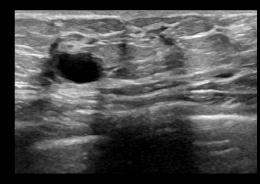

applyingMeanFilter,theresultisshowninFigure2(d).The outcome of the Median Filter is shown in Fig 2(e). Figure 2(f) depicts the outcome of using the Bilateral filter, while Figure 2(g) depicts the result of using the Anisotropic Diffusion filter, Figure 2(h) portraits the result of Total Variation filter and Figure 2(i) shows the result of NLM filter.

TheoriginalBUSimageisdisplayedinFigure2(a). The output of a Wiener Filter without FFT is shown in Figure2(b),whichusesa3x3kernel.Theresultofapplying the Wiener filter with FFT is shown in Figure 2(c). After

(a) (b) (c) (d) (e) (f) (g) (h) (i) Fig2.(a)Original BUSimage (d)MeanFilter (g)Anisotropic DiffusionFilter (b)WienerFilter withoutFFT (e)MedianFilter (h)TVFilter (c)WienerFilter withFFT (f)BilateralFilter (i)NLMFilter